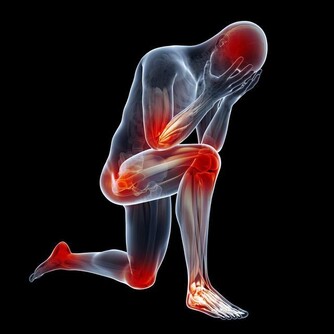

5.愛滋病的症狀?愛滋病症狀分為急性期、無症狀期和愛滋病期。

急性期:發生在初次感染後2至4週左右,表現為發熱、咽痛、噁心、嘔吐、淋巴結腫大等。

多數患者臨床症狀輕微,持續1至3週後緩解。

無症狀期:可從急性期進入此期,或無明顯的急性期症狀而直接進入此期。

此期持續時間一般為6-8年,其時間長短會因為個體差異而不同。

愛滋病期:主要表現為持續一個月以上的發熱、盜汗、腹瀉以及體重減輕,持續性全身淋巴結腫大。

部分病人還會出現記憶力減退、癲癇及癡獃等。